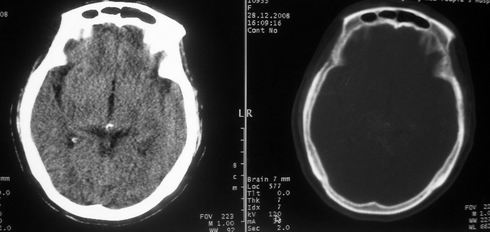

女,72岁,头晕。额骨有无问题。

考虑额骨良性骨板肥厚;骨纤待排。

左额部骨瘤

额骨呈磨玻璃状增厚,考虑骨纤。

额骨呈磨玻璃状增厚,考虑骨纤